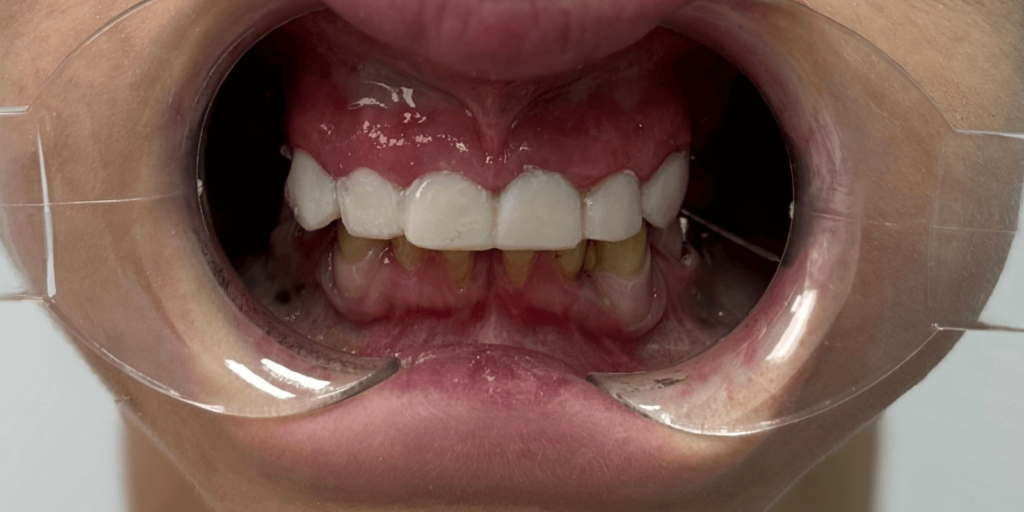

В нашу клинику обратилась женщина с многолетней усталостью в глазах. Она не могла нормально пережевывать пищу, стеснялась своей улыбки и постоянно подсознательно прятала лицо во время разговора. Ее беспокоили не только эстетические проблемы — отсутствуют зубы, старые мостовидные протезы, потемневшие пломбы, — но и функциональный дискомфорт, каждый день напоминавший о себе. Во время первичного осмотра (визуально) врач увидел:

- На верхней челюсти: 5 фронтальных зубов покрытых реставрационными пломбами, в области зубов 2.3-2.5 установлен металлокерамический мостовидный протез, 5 зубов отсутствуют. Установлен мостовидный протез в области зубов 1.4, 1.5, 1.6 с опорой на зубы 1.5 и 1.6. Зуб 1.7 покрыт металлокерамической коронкой.

- На нижней челюсти отсутствуют 5 зубов, передние зубы с большой тремой между ними, зубы 4.3 и 3.3 покрыты коронками из металлокерамики, на зубах 3.4, 3.5, 3.8 установлены большие корневые вкладки.